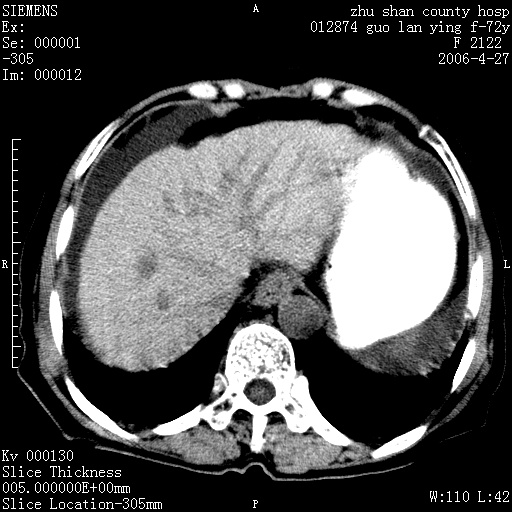

病人 女性 72岁 b超要求ct检查!

平扫所见:胆囊区两点壮高密度影,灶周有伪影{请问楼主患者有手术病史?}。肝实质内未见明显异常{建议强化或mri}.腹腔有少量积液,脾明显增大.右肾形态似不规则?

腹腔内示积液征,脾脏略增大,肝脏由于运动伪影较多,影响观察,内未见明显高密度区,胆囊内示两处高密度结石。胃窦部壁轻度增厚。另外,肝脏的前缘似有游历气体。不知病人的临床如何?有必要做胃的检查,还有,看看骨窗是否有腹腔游离气体还是肠管影响的。

如果b超对肝脏有怀疑,肝脏的增强扫描还是尽量去做。

肝脏缩小,脾脏增大,肝脾外缘及胆囊窝液性密度影,肝脾ct值正常,胆囊区见两个类圆形高密度影,下腔静脉前方类圆形软组织密度影为肝脏岛叶,胃幽门区见软组织密度影,十二指肠钡剂充盈不好.

1:腹水2:胆囊结石3肝硬化?(不确定,请结合临床)4幽门区占位?(建议胃肠透视)

肝硬化,脾大,少量腹水

肝硬化、脾肿大,腹水,胆囊区高密度影(结石或异物),是否有外伤史

肝硬化、腹水、脾大,胆囊结石可以肯定。只是肝右叶两个低密度有必要增强确定一下;排除小肝癌。

谢谢牟教授在百忙之中还认真的点评我的帖子!也谢谢大家的鼎力相助,此病人是我们医院护理部主任的母亲!病人以前无特别不舒适!昨天b超后发现有问题!做ct的目的在于排除肝内占位性病变,此病人以前无手术外伤史.